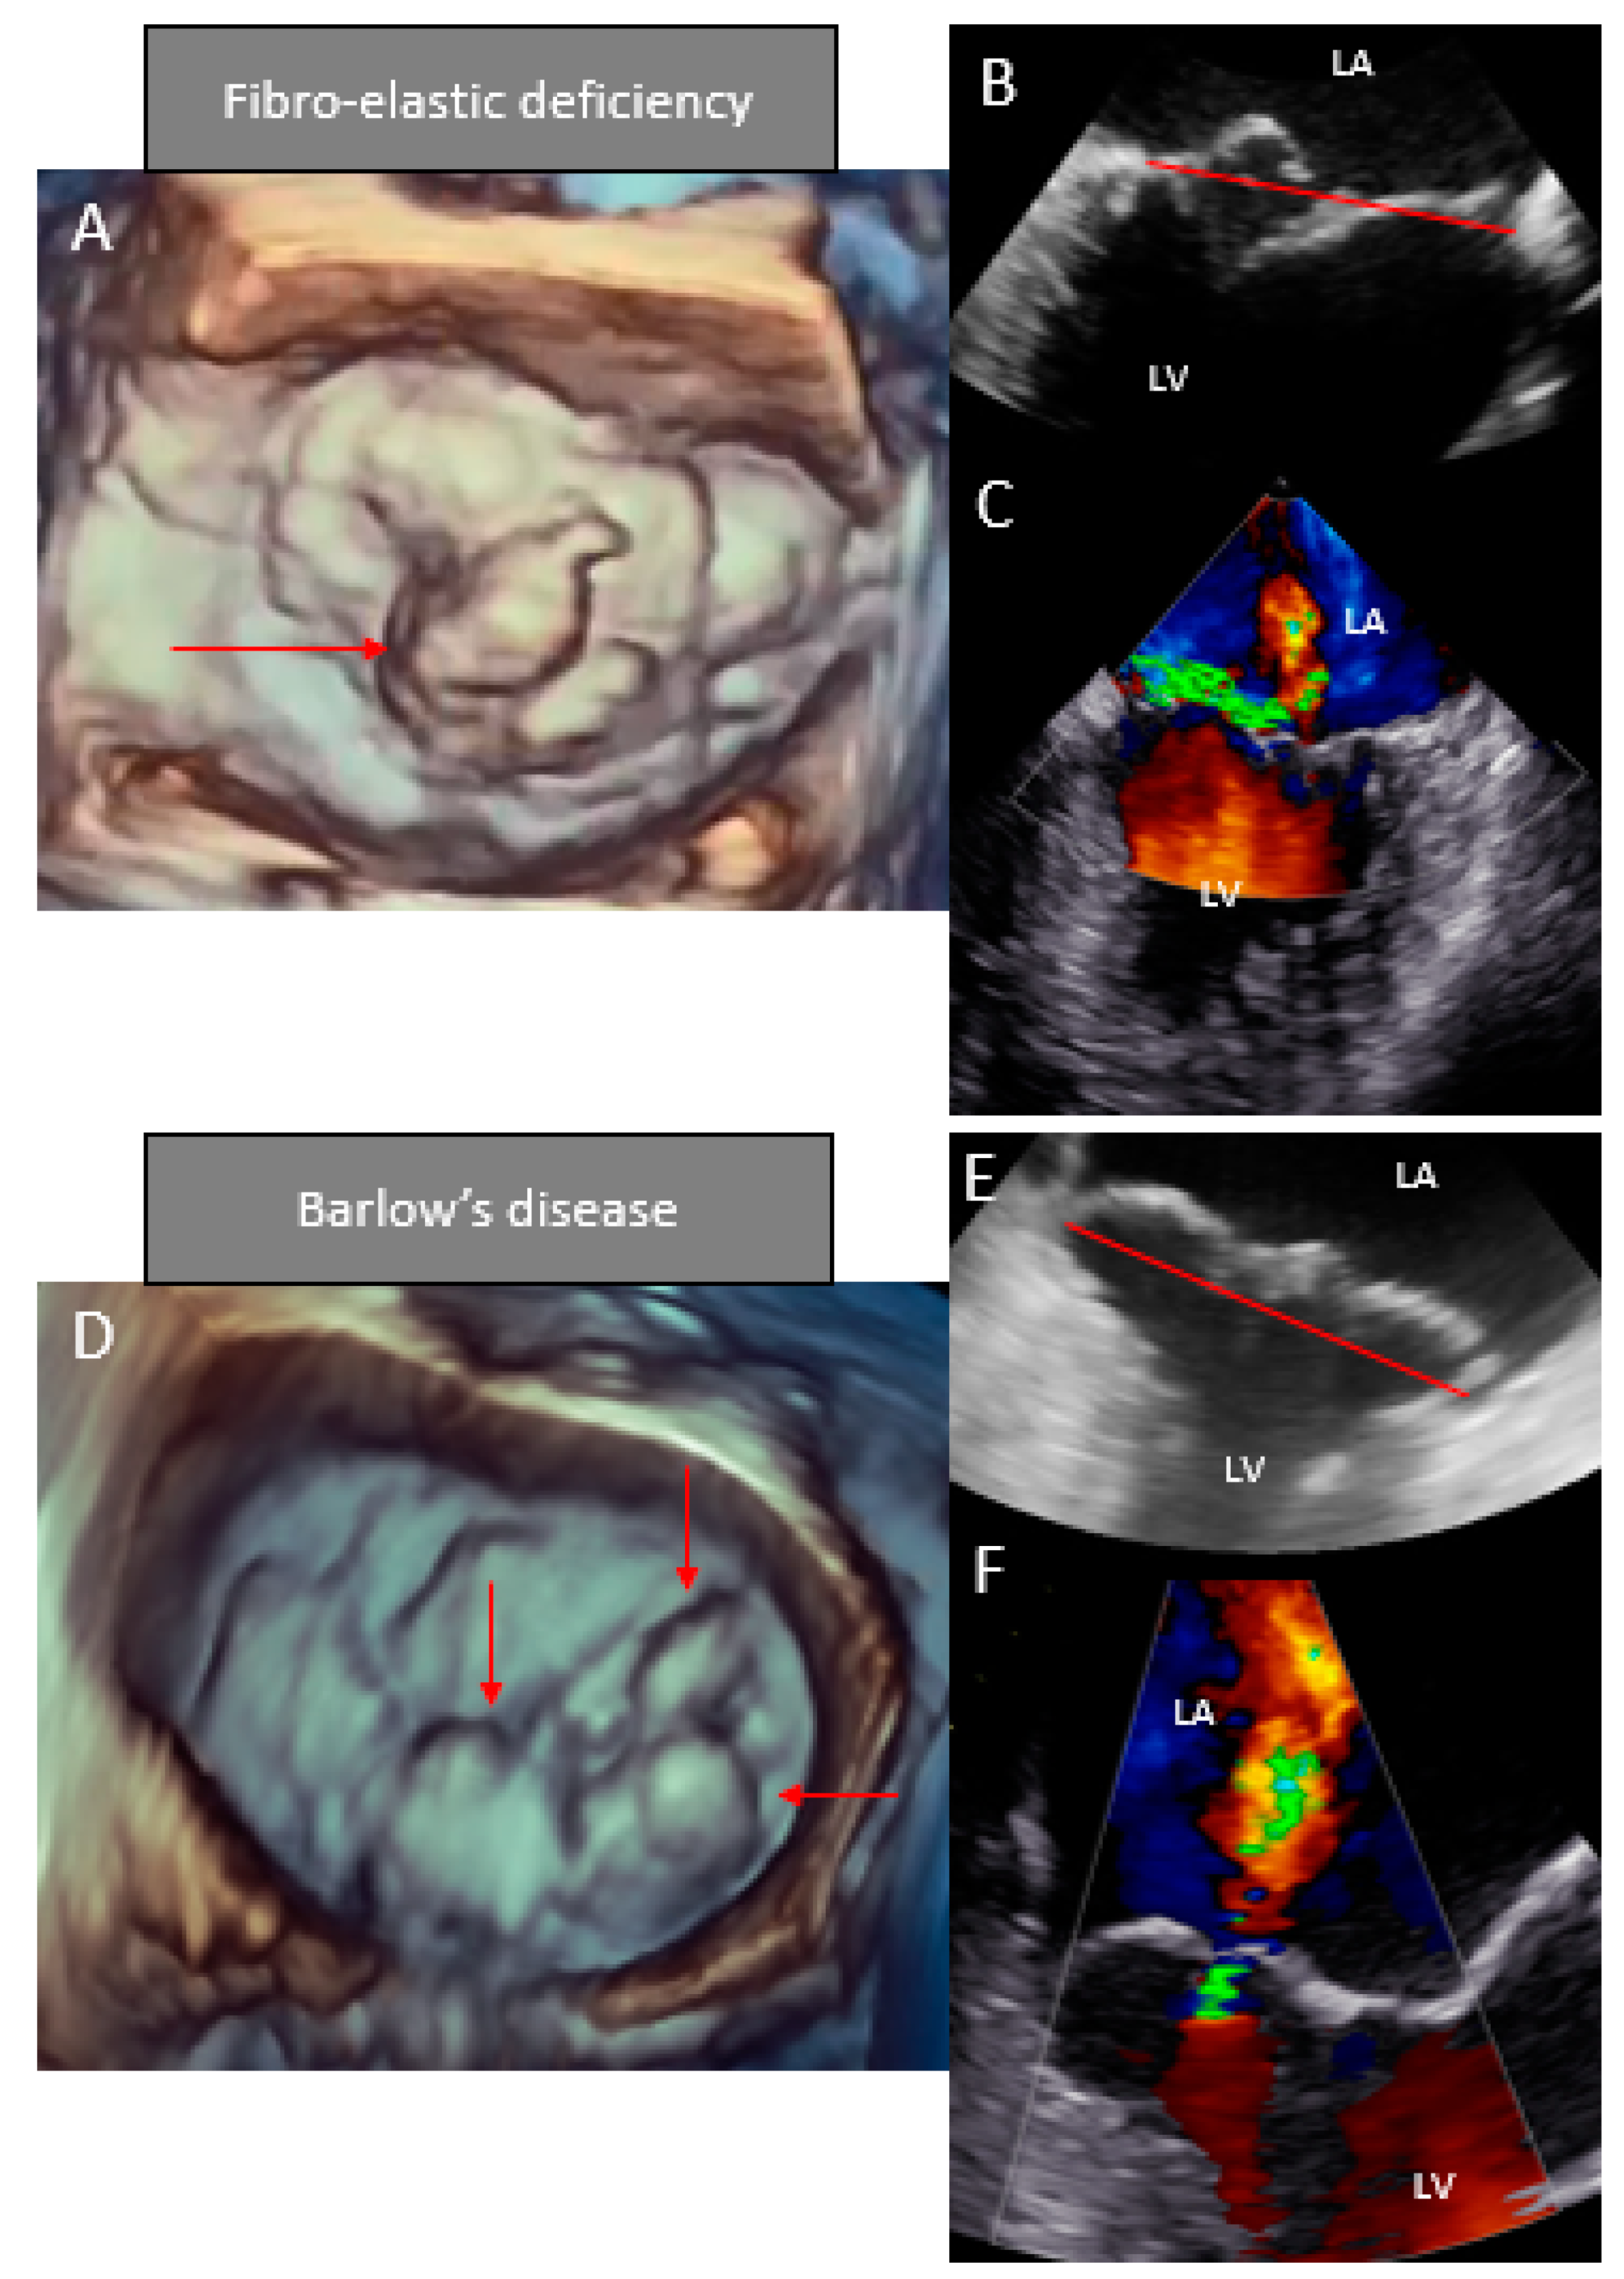

- Chandra, S.; Salgo, I.S.; Sugeng, L.; Weinert, L.; Tsang, W.; Takeuchi, M.; Spencer, K.T.; O’Connor, A.; Cardinale, M.; Settlemier, S.; et al. Characterization of degenerative mitral valve disease using morphologic analysis of real-time three-dimensional echocardiographic images: Objective insight into complexity and planning of mitral valve repair. Circ. Cardiovasc. Imaging 2011, 4, 24–32. [Google Scholar] [CrossRef]

- Carmo, P.; Andrade, M.J.; Aguiar, C.; Rodrigues, R.; Gouveia, R.; Silva, J.A. Mitral annular disjunction in myxomatous mitral valve disease: A relevant abnormality recognizable by transthoracic echocardiography. Cardiovasc. Ultrasound 2010, 8, 53. [Google Scholar] [CrossRef]

- Mantegazza, V.; Tamborini, G.; Muratori, M.; Gripari, P.; Fusini, L.; Italiano, G.; Volpato, V.; Sassi, V.; Pepi, M. Mitral Annular Disjunction in a Large Cohort of Patients with Mitral Valve Prolapse and Significant Regurgitation. JACC Cardiovasc. Imaging 2019, 12, 2278–2280. [Google Scholar] [CrossRef]

- Hiemstra, Y.L.; Tomsic, A.; Gripari, P.; van Wijngaarden, A.L.; van der Pas, S.L.; Palmen, M.; Klautz, R.J.M.; Pepi, M.; Bax, J.J.; Delgado, V.; et al. Evolution from mitral annular dysfunction to severe mitral regurgitation in Barlow’s disease. Interact. Cardiovasc. Thorac. Surg. 2020. [Google Scholar] [CrossRef]

| Leaflets | Single segment (usually posterior) prolapse (flail) due to chordal rupture Thickened leaflet tissue (when present) is limited to the level of the prolapsing segment Thin/normal leaflet tissue in non-prolapsing segments | Diffuse excessive valve tissue with multiple segments, bi-leaflet prolapse Thickened leaflets |

| Annulus | Normal of moderate annular dilatation No calcifications | Severe annular dilatation Calcifications could be present Mitral annular disjunction Systolic outward motion during systole (curling) |